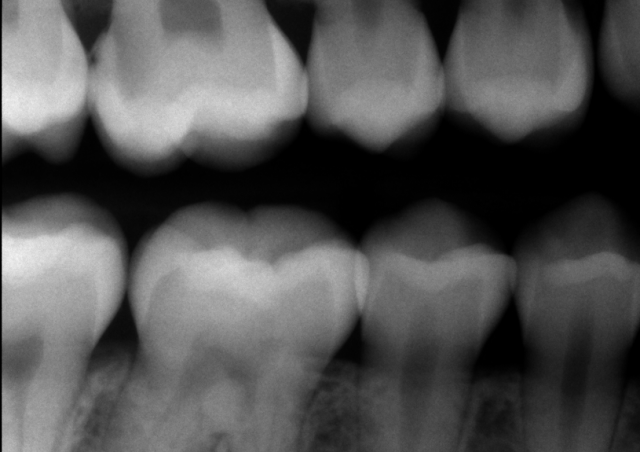

The first step in managing deep carious lesions is to determine the pulpal and periapical diagnosis of the tooth in question by performing pulp vitality testing. Pulpal diagnosis can be determined using a variety of tests, including “Endo Ice” cold testing, electronic pulp testing, and heat testing. Periapical diagnosis is achieved by determining if the tooth is symptomatic to percussion or palpation or if a periapical radiograph shows asymptomatic periapical pathology.

In the event a tooth presents with irreversible pulpitis, pulpal necrosis, or periapical pathology, endodontic treatment must be pursued. However, if the tooth is asymptomatic, caries excavation and restoration can be considered.

If a tooth with a deep carious lesion presents with a normal pulp and periapical tissue, there are various ways to excavate the decay.